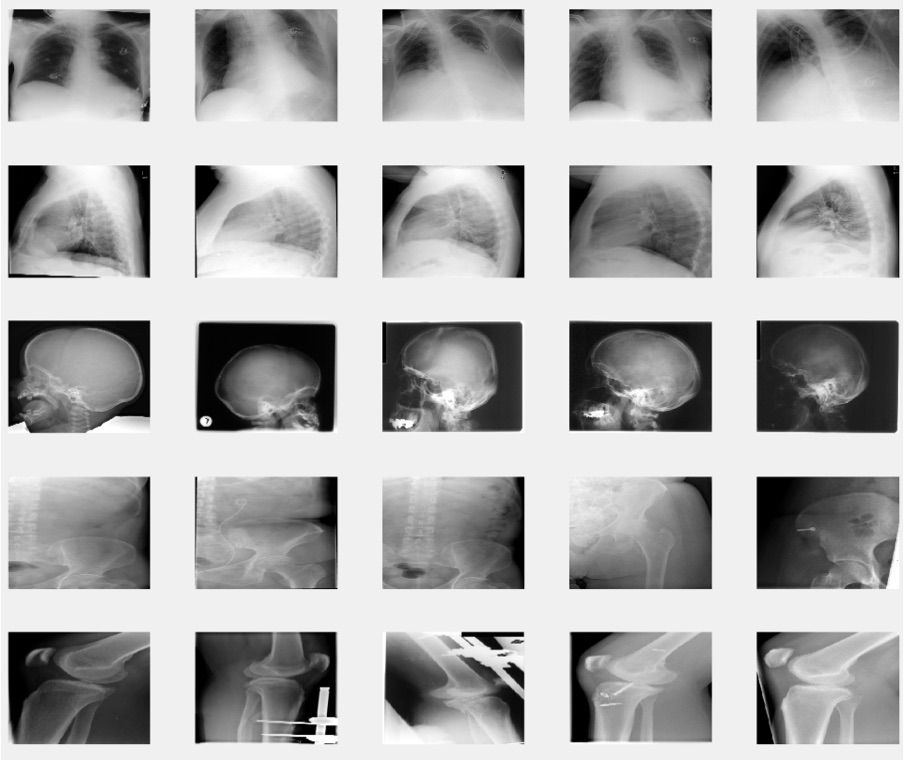

In this paper the image Retrieval in Medical Applications (IRMA) database [25] the benchmark dataset from ImageCLEFmed09, a retrieval challenge in a collection of medical images, is used to validate the proposed method. The IRMA database is a collection of more than 14,000 x-ray images (radiographs) randomly collected from daily routine work which is used for training and testing. All the images were classified in 57 categories and annotated with the IRMA code. The IRMA codes (manually created by several clinicians), which is a string of 13 characters within the set of 0, ,9,a, ,z, contain information on technical, biological and diagnostic traits of the image in a structured manner: TTTT-DDD-AAA-BBB. Figure 2 shows some sample images in the IRMA dataset with their corresponding IRMA code.

Refer to caption

Figure 2: Sample images from IRMA dataset with their IRMA codes.

In this dataset, a total of 12,677 x-ray images is used for training and the remaining 1,733 images are considered as testing data. The distribution of data in training and testing images shows that there exists considerable imbalance in IRMA dataset (Figure 3).